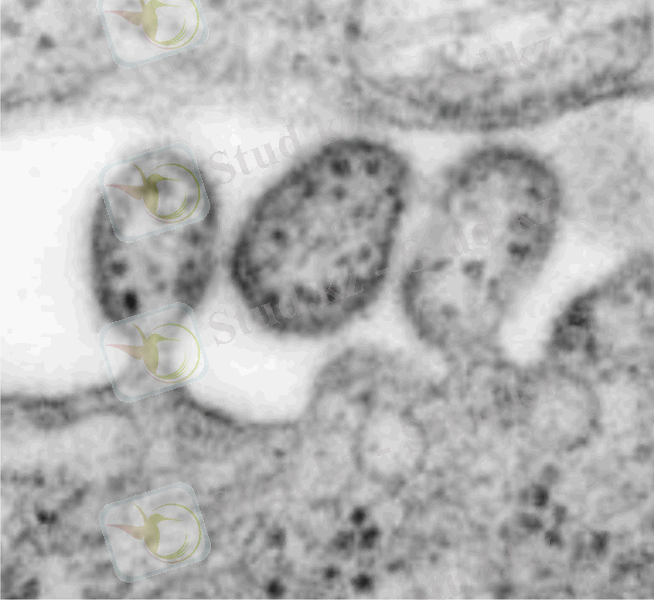

Бұл көптеген жедел жұқпалы аурулар тобы, осыларды біріктіретіні вирусты этиологиялығы, табиғи ошақтығы, айқын капиллярдың эндотелиінің зақымдалуы, геморрагиялық синдромының дамуы.

Вирус денеге кене шаққанда тері арқылы түседі. Вирустың тропизмдік қасиеті гипоталамикалық ортаға және вазотроптік (зақымдайды бүйрек, бауыр және ОЖЖ ұсақ тамырларының эндотелиін) . Осының нәтижесінде қантамырлардың өткізгіштігі жоғарылайды, қанның ұю жүйесінің қызметі бұзылады «ТІШҚҰң- дамиды. Сонымен қатар сүйек миының клеткаларының өсуі басылады, бауырдың функциясы бұзылады.